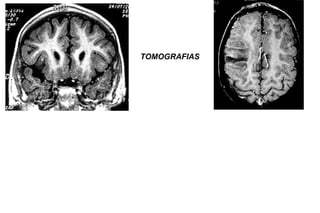

TOMOGRAFIAS